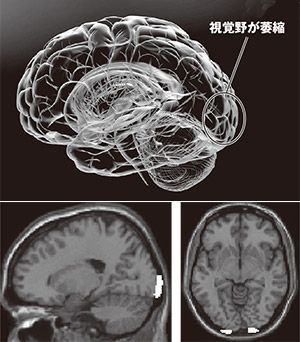

(上)面前DVによるマルトリートメントの脳への影響(下)白い部分は容積の減少が見られた視覚野の一部(写真提供=友田明美氏)